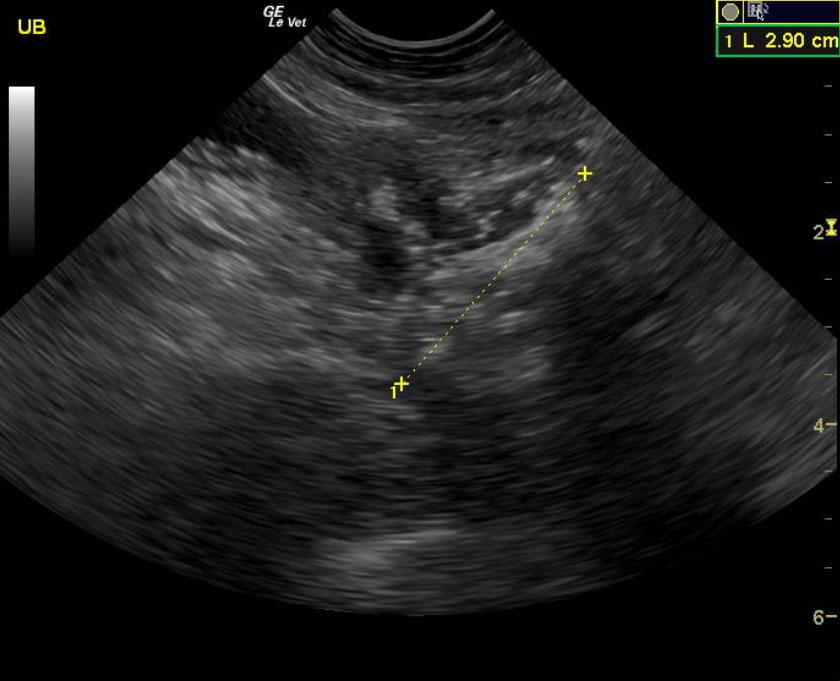

An 11-year-old neutered male Pomeranian dog was presented for evaluation of tenesmus, “hunched” stance, and decreased energy. On physical examination, a 3cm palpable mass cranial to pelvic canal was noted. Survey radiographs showed a mineralization/spherical mass in area of the prostate.

The prostate presented multi focal mineralization with swollen contour with minor polypoid changes and hyperechoic surrounding fat. This projected into the trigone. The mineralizing, prostatic mass measured 2.9 cm and infiltrated into the preprostatic urethra and likely post prostatic urethra. Iliac lymphadenopathy was noted.